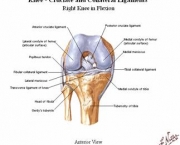

Também conhecida como gonartrose, a osteoartrose do joelho é uma enfermidade degenerativa e inflamatória que resulta na destruição da cartilagem das articulações levando à deformidades nelas. Normalmente a degeneração cartilaginosa começa com o envelhecimento do indivíduo.